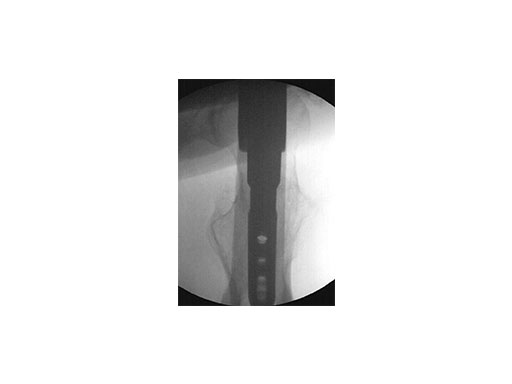

Use of metallic instruments limits the surgeon's view during fluoroscopy, resulting in difficulty visualizing the fracture and the proper positioning of the locking mechanisms in the bone. The new insertion handles have an increased radiolucent area (Fig 1). In the US, the Standard Insertion Handle is used for the LFN-EX, R/AFN-EX, and Expert Tibial Nail. The shorter Dedicated Tibia Insertion Handle is optional for tibia procedures. Together with the radiolucent aiming arms (Fig 2), the visualization of the relevant bony anatomy on intraoperative x-ray images is improved (Fig 3). The new aiming arms have built in retention mechanisms and cam locks, which allow true-locking of the protection sleeves to decrease the risk of accidental loosening of the parts during the procedure.